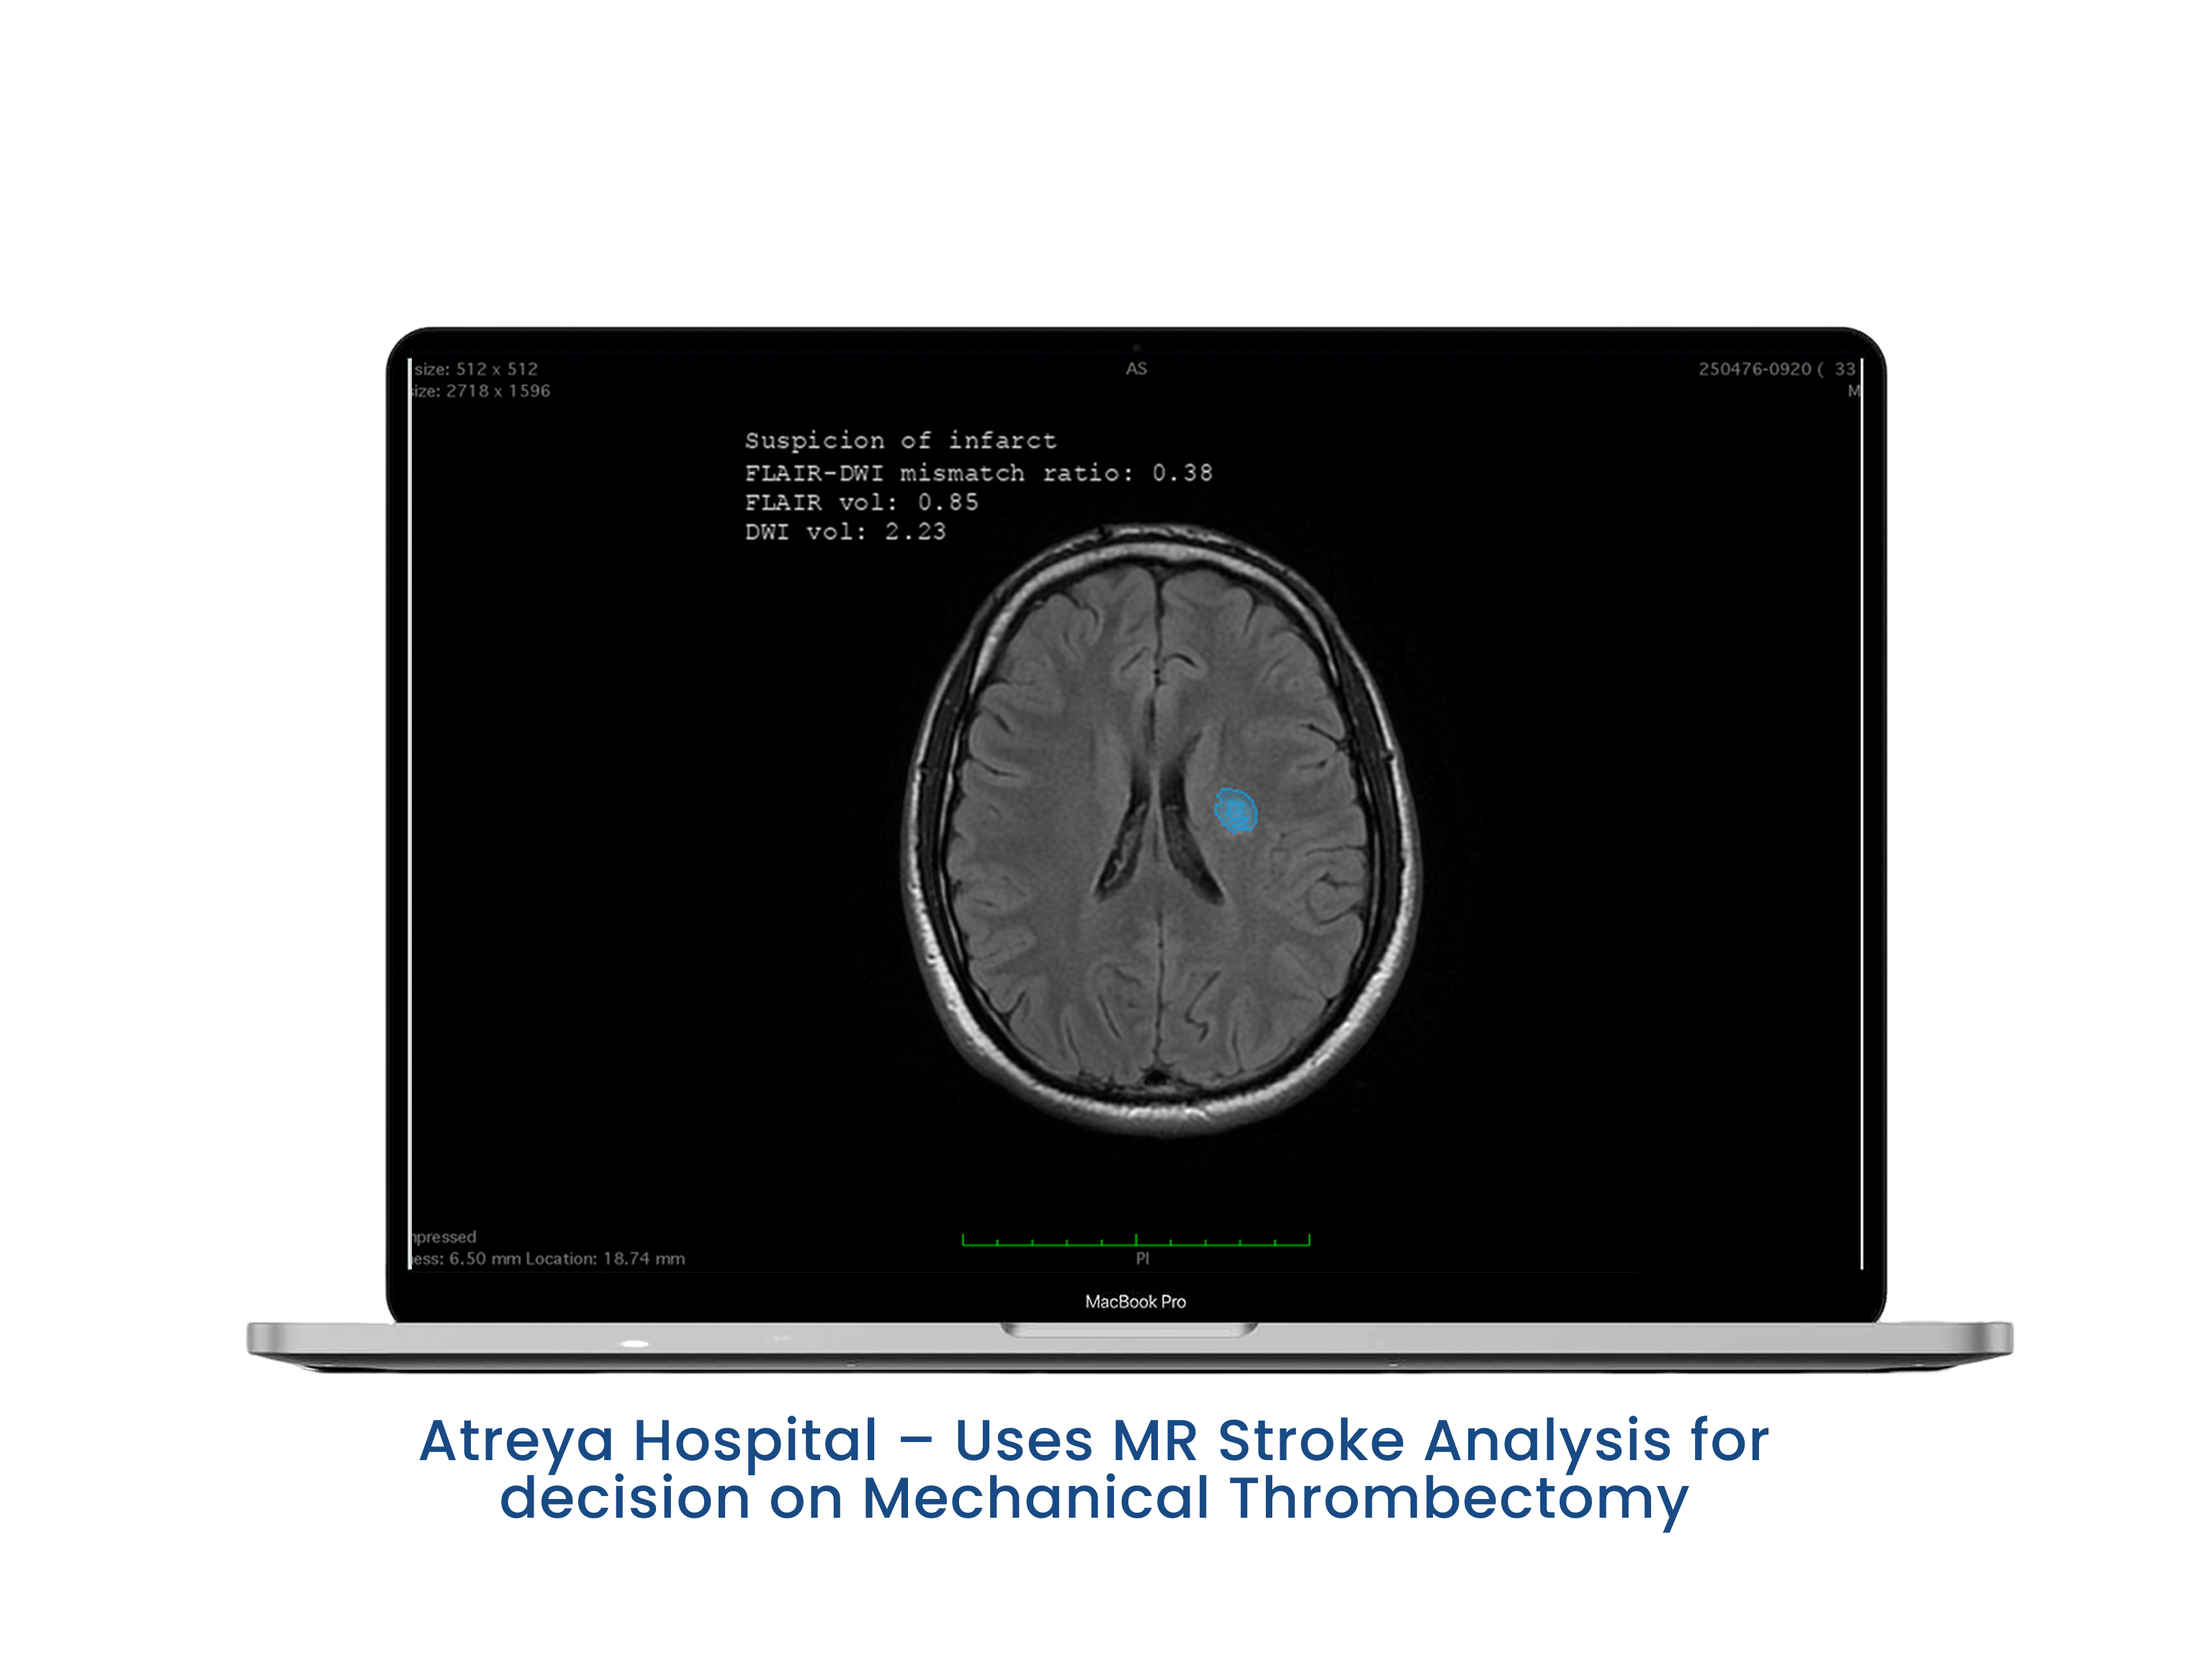

AI Enhancement for CT, MR

AI segmentation Module for different anatomies and abnormalities